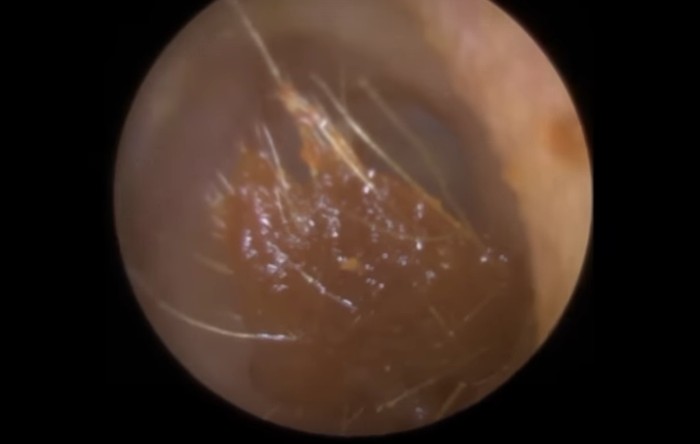

Begini bentuk salah satu kotoran telinga manusia. Berwarna coklat dan agak lengket. (Foto: YouTube)